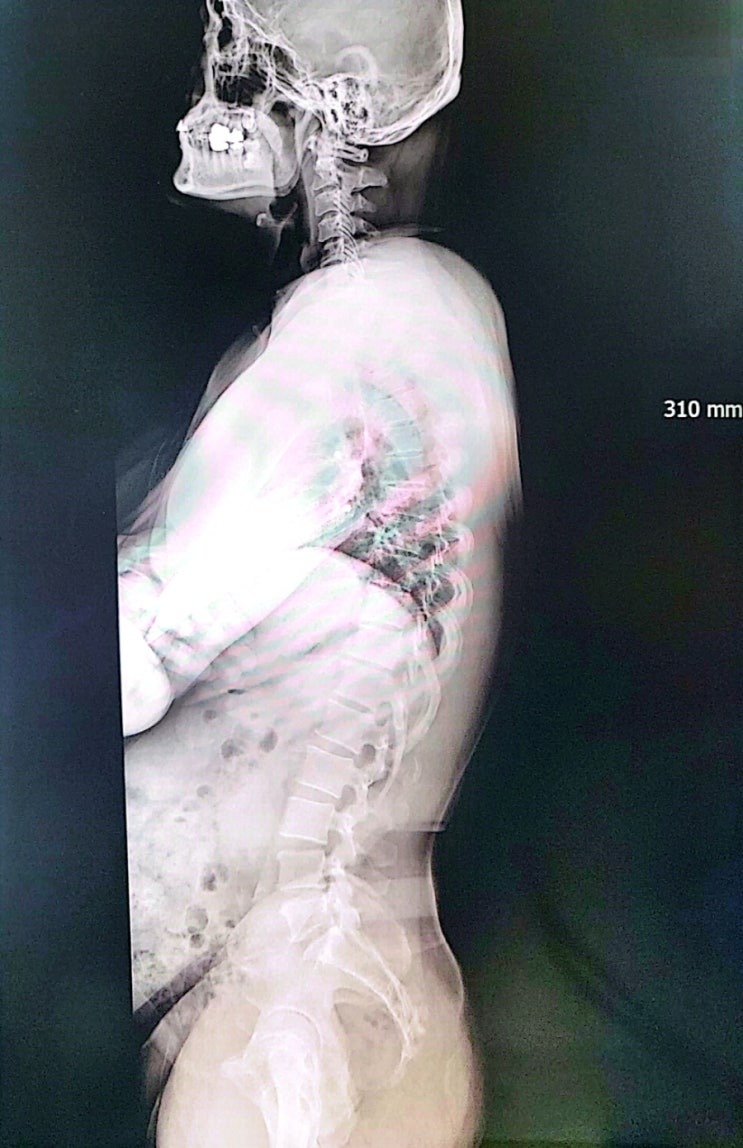

거북 목과 급은 등